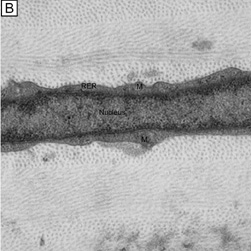

The corneal stroma is maintained by a closed, highly-organized syncytium of keratocytes communicating with each other through gap junctions present on their long dendritic processes.68 Keratocytes occupy 10% to 40% of the stromal volume (decreases from 40% in infancy to 10% in adulthood) that on two-dimensional, cross-sectional views appear as flattened (cell body = 20 μm in length × 1 μm in height), quiescent (i.e., scant intracytoplasmic organelles) cells lying between corneal lamella (Fig. 16A, B). In actuality, keratocytes are three-dimensional, stellate-shaped cells composed of a cell body (≅1 × 15 × 20 μm) with numerous dendritic-processes that extend up to 50 μm in length from the cell body. Two-dimensional tangential sections of the normal cornea suggest that these cells are more highly metabolically active in the resting state than initially presumed; in tangential sections (cell body view = 15 μm width × 20 μm), an abundance of cytoplasmic organelles is commonly seen (Fig. 16C, D).69

Fig. 16. Light and TEM micrographs shown in cross and frontal-sectional views of the cellular corneal stroma demonstrating differences in the appearance of keratocytes depending on the cut, or perspective, of the section. (A) Cross-sectional light microscopy shows that keratocytes are primarily obliquely aligned to corneal surface in the anterior one-third of cellular corneal stroma and are aligned parallel to the corneal surface in the posterior two-thirds. (B) Cross-sectional TEM additionally shows that keratocyte nuclei occupy most of the area of the keratocyte seen in this perspective with only a thin rim of surrounding cytoplasm that contains only small numbers of cytoplasmic organelles. (C) From a tangential perspective, frontal-section light microscopy shows that keratocytes are arranged in a circular fashion. (D) Frontal-section TEM additionally shows that supposedly quiescent keratacytes may be more active in the baseline state than initially thought as an extensive amount of cytoplasmic organelles can be seen in this view. M, mitochondria; RER, rough endoplasmic reticulum; V, vacuoles. *Main portion of nucleus that contains nucleolus. (Modified from Muller LJ, et al. Novel aspects of the ultrastructural organization of human corneal keratocytes. Invest Ophthalmol Vis Sci 36:2557, 1995.)